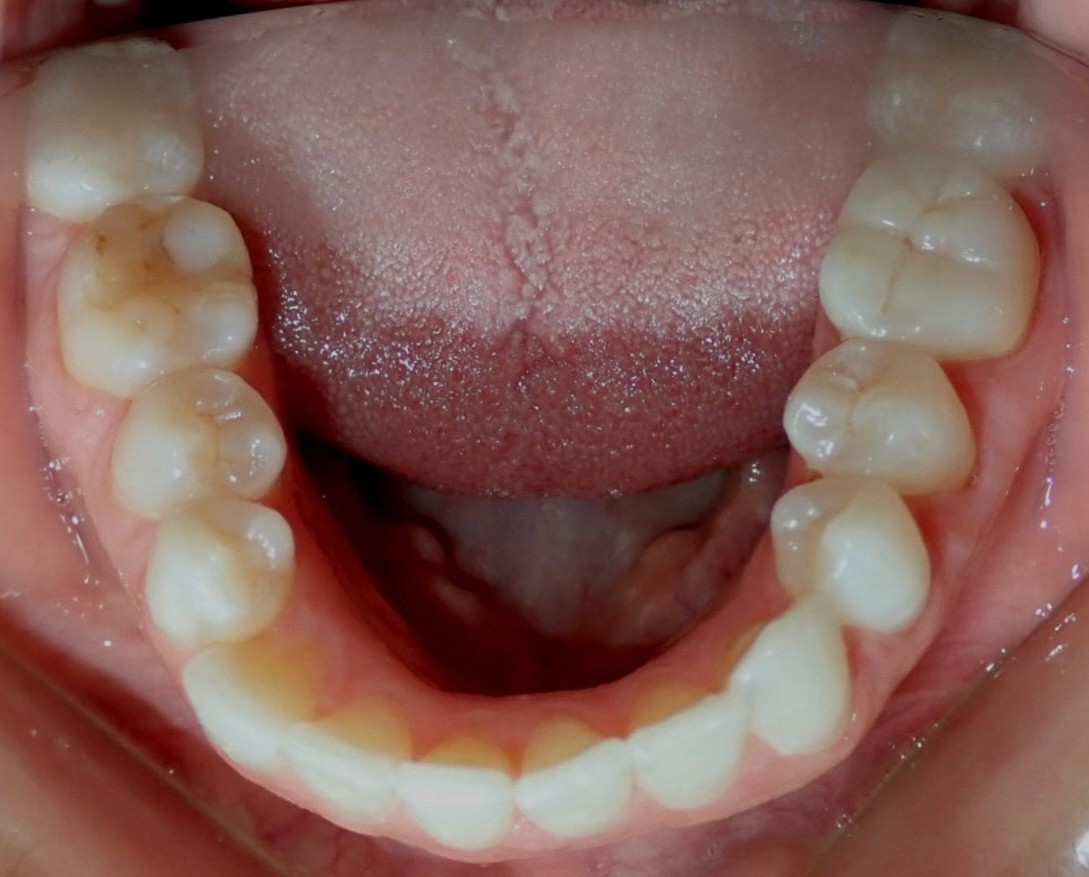

Initial treatment

INTRAORAL